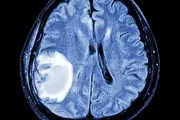

Medical experts reveal four crucial head-related symptoms that could indicate a brain tumour, urging immediate medical attention for persistent issues.

Medical experts reveal the subtle yet crucial symptoms that could indicate a brain tumour, urging Brits not to dismiss persistent headaches, fatigue and cognitive changes.

Experts reveal the subtle symptoms that could indicate a brain tumour, from personality changes to vision problems. Learn when to seek medical attention.